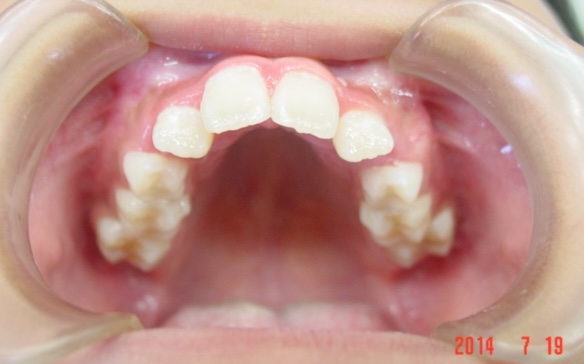

矯正前

| 症状 | 上顎前突 |

| 通院目的 | 永久歯を抜かずに歯並びを治したい。 |

| 処置内容 | バイトブロック・プレート拡大処置・クリアアライナー・マルチブラケット装置・プレート拡大付き切歯斜面板・SHA・ディスタライザー・インビザライン |